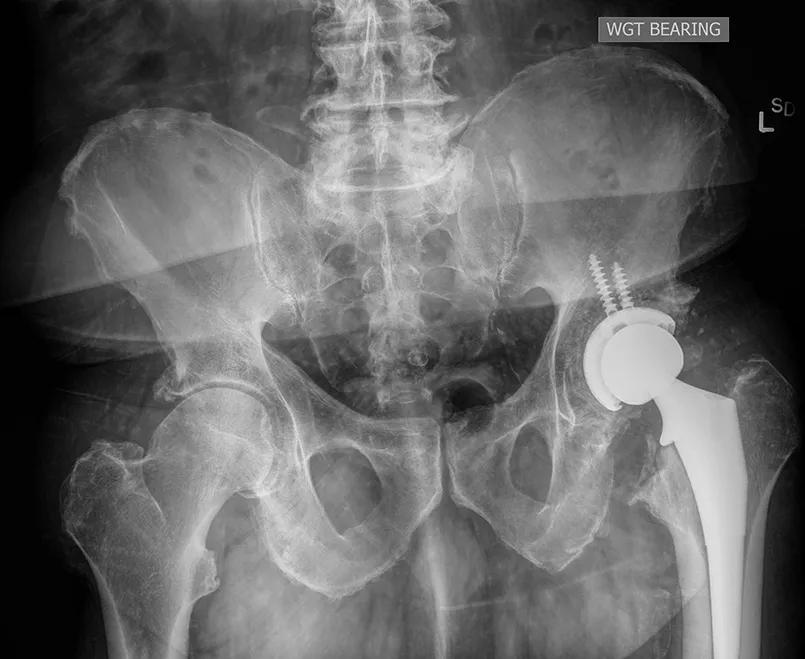

Total hip replacement

The outcomes of direct anterior hip replacement may be equivalent to conventional hip replacement using lateral or posterior approaches, but demand for the direct anterior approach has soared in recent years.